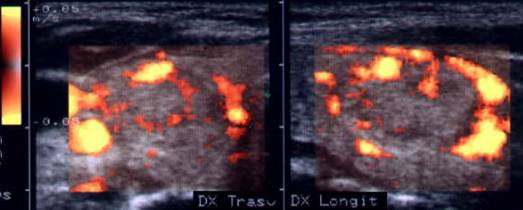

Femeie 26 ani. Nodul mare de consistenta crescuta de 14 cc, care ocupa quasi complet lobul drept; contur net, neomogen, micro si macrocalcificari. Citoaspiratie – nodul hiperplazic

Aceeasi pacienta.Vascolarizatie periferica si

intranodulara.